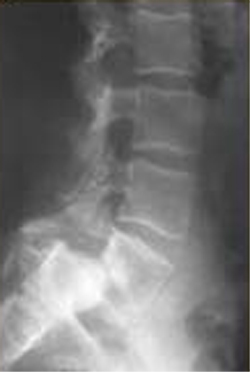

30. A 71-year-old female who has no significant medical comorbidities presents to the emergency department after sustaining a compression fracture of L2. The patient has moderate back pain but is neurologically intact. Radiographs of the entire spine reveal a L2 compression fracture with 30% loss of vertebral body height loss and 15 degrees of local kyphosis. What would be the appropriate management for this patient?

DISCUSSION: Initial treatment of osteoporotic compression fractures without neurologic compromise consists of pain control, progressive increase in activity levels, and a TLSO, or thoracolumbosacral orthosis.

Compression fractures are common in the elderly with osteoporosis as a result of low energy trauma. Most of these can be managed without surgery in a brace and oral pain medication. Initial management consists of pain control and a gradual return to activity. If pain continues after 6 weeks of non-operative therapy, kyphoplasty or vertebroplasty are available options. If a neurologic deficit is present, management would include surgical decompression and stabilization.